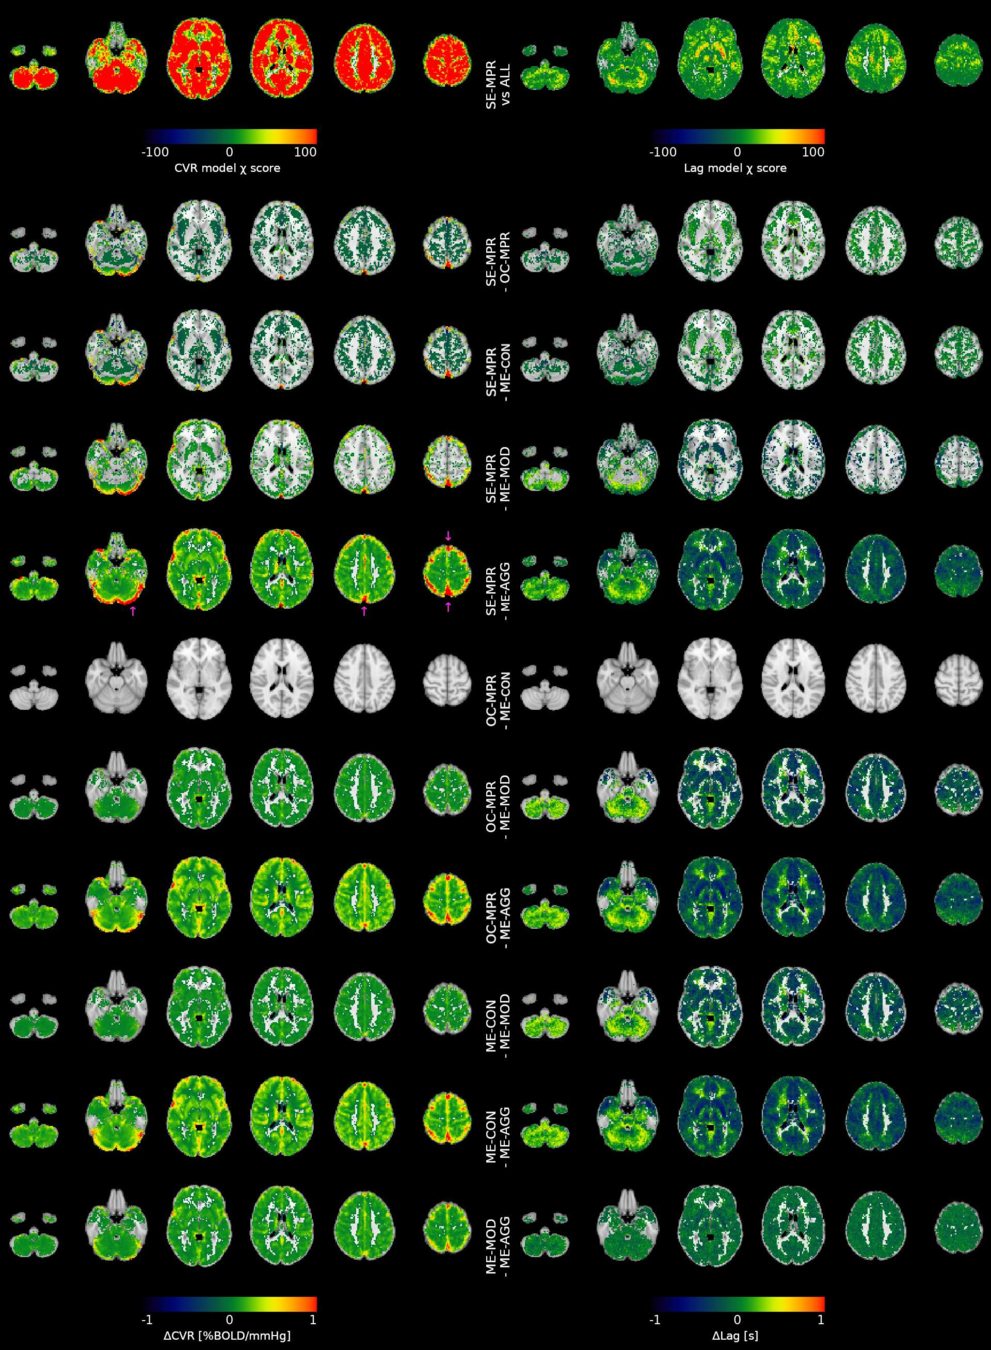

Results: model comparison

Moia et al. 2021 (NeuroImage)

CVR amplitude

CVR lag

CVR amplitude

CVR lag

Results: model comparison

Moia et al. 2021 (NeuroImage)

CVR amplitude

CVR lag

CVR amplitude

CVR lag

Results: model comparison

Moia et al. 2021 (NeuroImage)

CVR amplitude

CVR lag

CVR amplitude

CVR lag